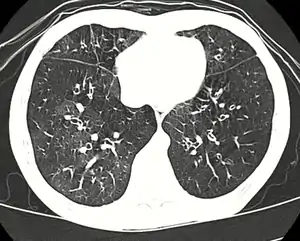

| High resolution CT scan showing bronchiolitis obliterans with mosaic attentuation, bronchiectasis, air trapping and bronchial thickening[3] | |

Early in the disease chest radiography is typically normal but may show hyperinflation.[6] As the disease progresses a reticular pattern with thickening of airway walls may be present.[4][6] HRCT can also show air trapping when the person being scanned breathes out completely; it can also show thickening in the airway and haziness in the lungs.[11] A common finding on HRCT is patchy areas of decreased lung density, signifying reduced vascular caliber and air trapping.[6] This pattern is often described as a "mosaic pattern", and may indicate obliterative bronchiolitis.[6]